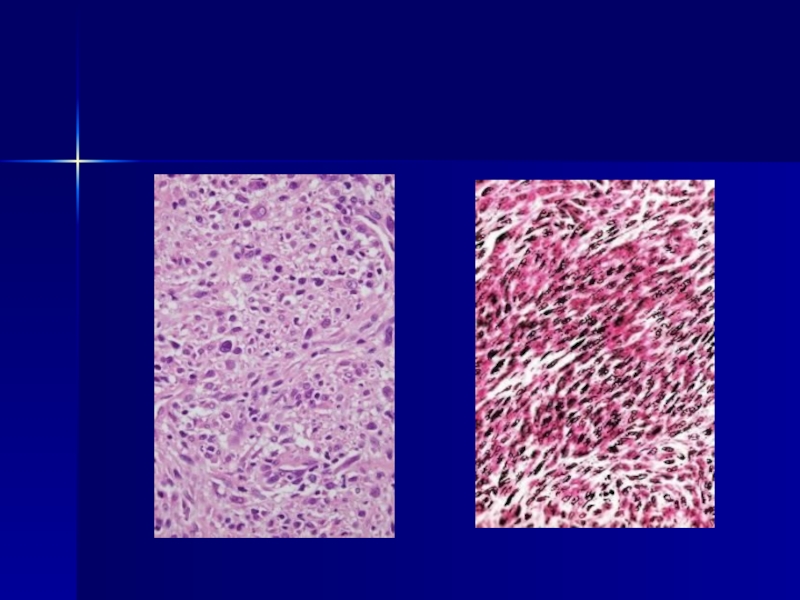

Слайд 16Классификация меланом

Особые формы

Десмопластическая

Нейротропная

Баллонная

Минимально отклоненная форма